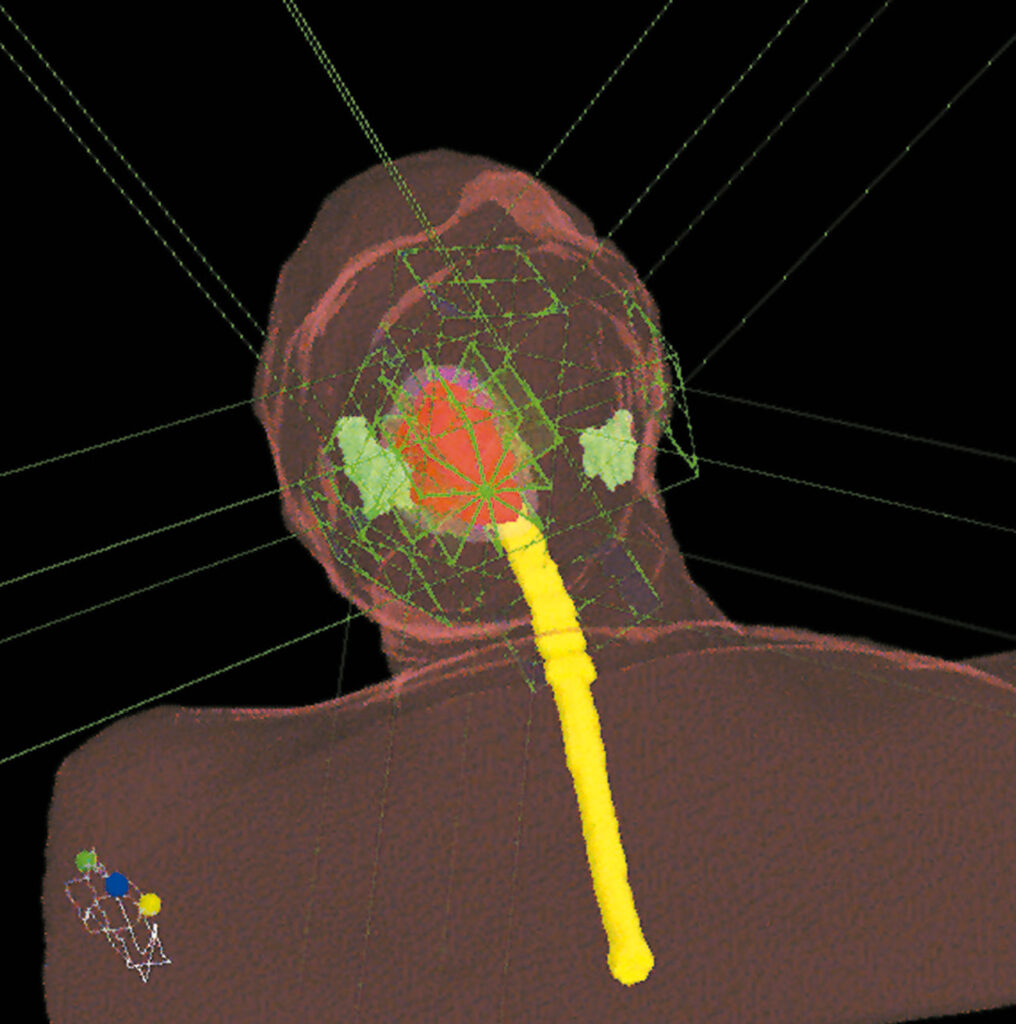

Los médicos radioterapeutas delinean los volúmenes de interés, tumor y órganos sanos, definen las funciones objetivos, es decir, establecen las relaciones Dosis-Volumen que desean obtener y adoptan una estrategia de fraccionamiento apropiada. Luego se diseña una configuración de múltiples haces.

IMRT emplea por primera vez en Radioterapia el concepto “Planificación Inversa”, en la cual, a diferencia de métodos anteriores, los médicos prescriben en la etapa inicial cuáles son los resultados deseados en términos de relaciones Dosis-Volumen y la estación de trabajo IMRT converge a la solución propuesta, obteniéndose mapas de campos de intensidades variables mediante un complejo proceso de iteración.

La Planificación Inversa ofrece el escenario óptimo para tratar a cada paciente en particular, liberando altas dosis en el tumor y minimizando la dosis en los tejidos sanos.